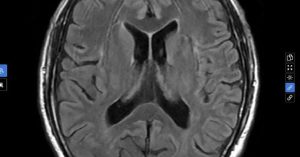

Nhìn mờ thoáng qua rồi tự hết cũng có thể là dấu hiệu đột quỵ nguy hiểm, vì sao?

Nam bệnh nhân 67 tuổi, quốc tịch Nhật Bản, bất ngờ xuất hiện tình trạng...